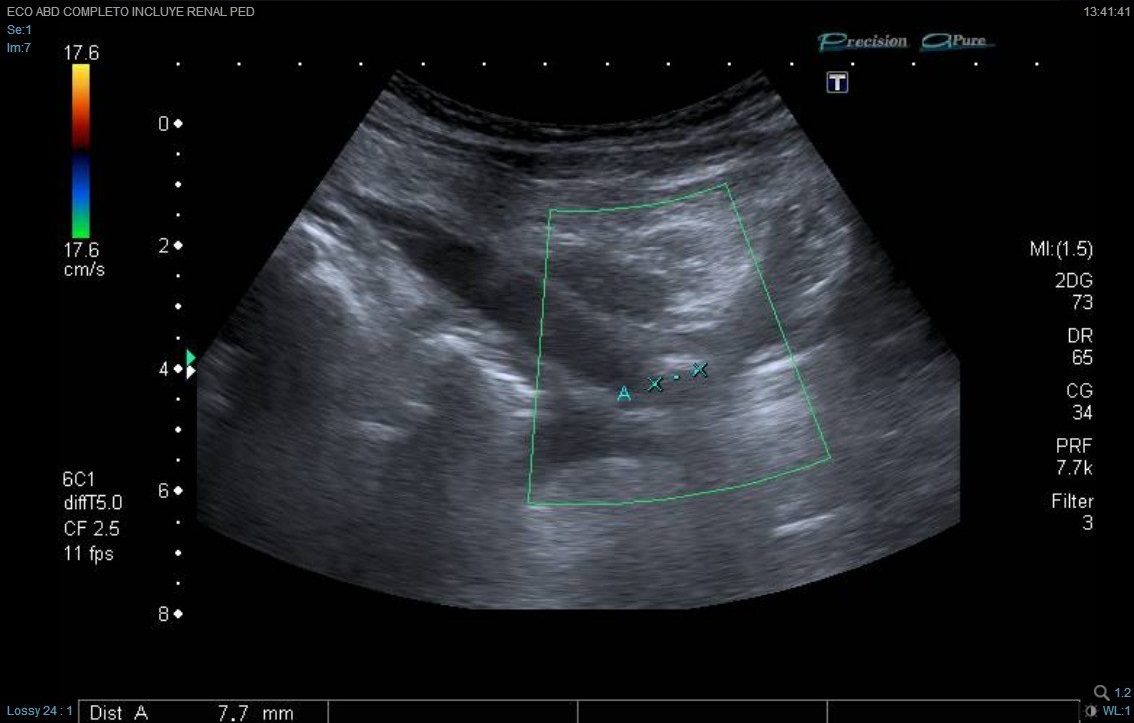

Ante los vómitos y la exploración abdominal se solicitaron: sedimento de orina pH 5, densidad 1030, hematíes 150/µl, proteínas 75 mg/dl, uratos amorfos; hemograma normal; química (función renal, proteínas totales, albúmina, electrolitos incluyendo Na, K, Cl, Ca, Mg, fósforo) normal; urinocultivo negativo; coprocultivo y virus en heces negativo; radiografía de abdomen normal, no se visualiza imagen de litiasis; ecografía abdominal (Figs. 1 y 2): cálculo de 7-8 mm, casi en el meato ureteral derecho, a 5-6 mm de la vejiga, con moderada ureterohidronefrosis proximal. No había líquido libre intraperitoneal. No se observa apéndice engrosado. El riñón y la vía excretora urinaria izquierdos no mostraban alteraciones.

La ecografía ha supuesto un gran avance en el diagnóstico de los cálculos, especialmente en niños, en los que suelen ser de pequeño tamaño. El aspecto típico es el de una imagen hiperecogénica con sombra sónica posterior.